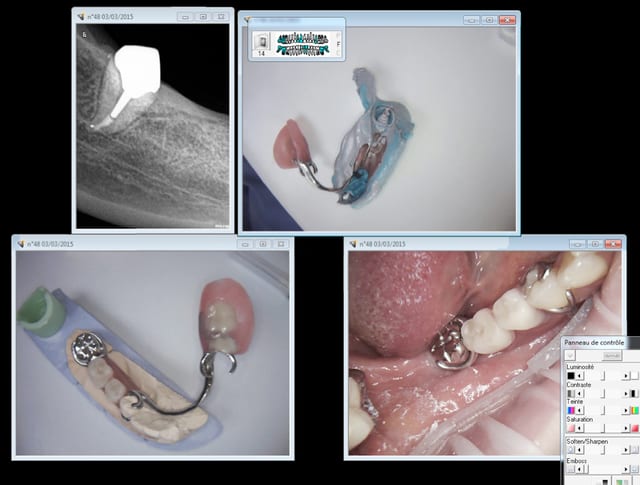

Tu t'occupes de santé publique, hein ? Alors je vais t'expliquer comment ca se passe à long terme sur le terrain grace à la merveilleuse nomenclature de ce système collectiviste de merde :

Endo pourries à un tarif de merde- coiffes...... extractions........ bridge ......... extractions- complet immédiat.

Tu es sur que tu sers à quelque chose ? quelle réussite ! -))))

Big up pour la CCAM ultra moderne ( bridges) qui va dans le bon sens !

Ca fait toujours son effet un complet immédiat, un plaisir à gérer pour le praticien et le patient !

Capture d e cran 2015 03 02 21.50 - Eugenol

Capture d e cran 2015 03 02 21.52 - Eugenol

Apparement ,nos tetes pensantes ont décidés qu'il était plus simple

de leur donner le DROIT d'avoir du 4 à 4 céramisés (payés 8000 euros pour les 2 arcades) plutot que le DEVOIR d'utiliser une brosse à dent souples à 4 euros .